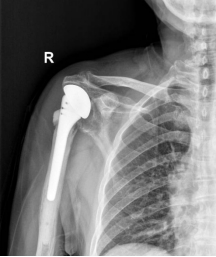

术前X线片